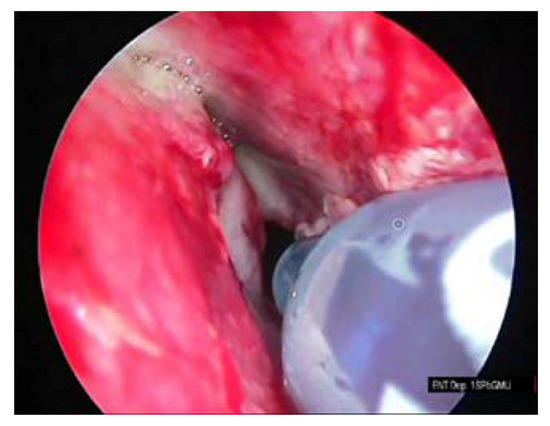

The procedure of the sphenoid sinus volume based on CT scanning followed by 3D reconstruction is illustrated in Figure 1. The corresponding intraoperative measurement procedures are illustrated in Figure 2, Figure 3 and Figure 4.

Figure 2. Filling of the sphenoid sinus with 0.01% methylene blue solution with the insulin syringe.